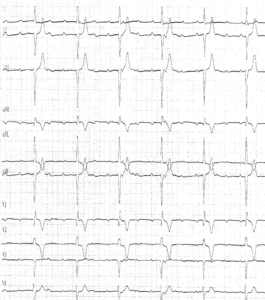

Le diagnostic de BAV complet se définit par l’interruption complète de la conduction auriculo-ventriculaire et repose sur l’existence d’une dissociation auriculo- ventriculaire, les oreillettes et les ventricules étant sous le contrôle de pacemakers indépendants, avec une fréquence ventriculaire plus lente que la fréquence auriculaire. Il n’existe pas de relation entre les ondes P et les complexes QRS, les intervalles PR sont variables sans séquence répétitive.

La fréquence de l’échappement ventriculaire est généralement régulière, non ou peu influencée par les efforts ou les manœuvres vagales. La fréquence et la durée du QRS varient en fonction du site d’échappement:

• échappement jonctionnel: l’origine de l’échappement étant haut située au dessus de la bifurcation du faisceau de His, la durée des complexes QRS est normale (inférieure à 100 ms) sauf si il existe un bloc de branche préexistant (comme chez ce patient); la fréquence ventriculaire est généralement modérément ralentie (entre 40 et 50 battements par minute);

• échappement du faisceau de His ou d’une des branches: l’origine de l’échappement étant située soit au niveau du faisceau de His, soit au-dessous de la bifurcation sur une des branches, le QRS peut être fin (échappement du His) ou large avec un aspect de boc de branche (His + bloc de branche ou échappement d’une branche); la fréquence ventriculaire est généralement ralentie (entre 30 et 40 battements par minute);

• échappement ventriculaire: l’origine de l’échappement étant bas située et correspondant à un foyer idioventriculaire, la durée des complexes QRS est très élargie (entre 140 et 200 ms) et ne rappelle que très grossièrement l’aspect d’un bloc de branche et est qualifiée de retard droit ou de retard gauche; la fréquence ventriculaire est très ralentie (parfois inférieure à 20 battements par minute).

Le rythme auriculaire est le plus souvent sinusal même si on peut observer une fibrillation auriculaire ou un flutter atrial. Le rythme sinusal est parfois accéléré, la fréquence auriculaire ayant tendance à être d’autant plus rapide que la fréquence ventriculaire est lente par une réaction réflexe du nœud sinusal à la bradycardie ventriculaire.